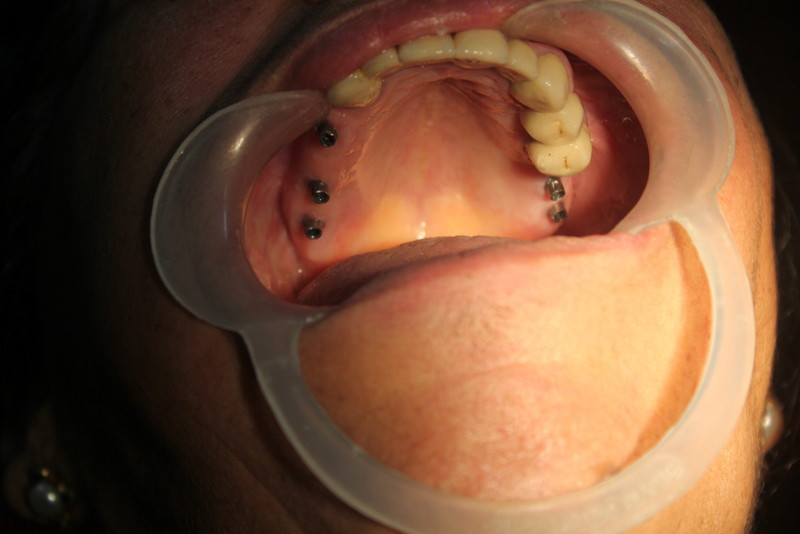

Bilateral Direct Sinus Lifts